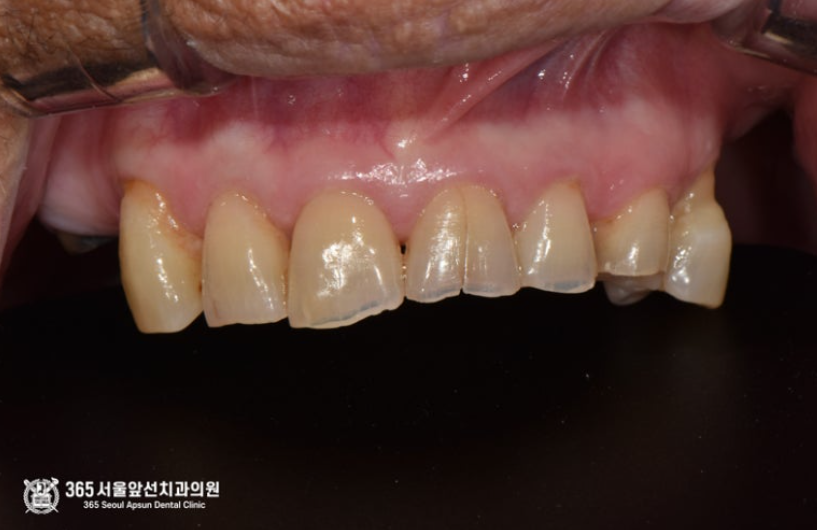

앞니가 깨지고 갈라져서 보기싫어요. 앞니가 예뻐졌으면 좋겠어요. 앞니의 미용적인 문제를 호소하시며 환자분께서 내원하셨습니다. 앞니의 미용적인 문제를 해결하는 방법에는 여러가지 치료적 접근법이 있습니다. 예를들자면, 라미네이트와 같은 비니어(veneer)를 이용하여 얇은 도자기를 치아 위에 입히는 방식, 크라운(crown)이라고 부르는 치아를 360도 감싸는 형태의 보철물로 치료하는 방식, 레진(composite resin)을 이용하여 수작업을 통해 치료하는 방식 등이 있겠습니다. 상기 환자분의 경우, 복합레진(composite resin)을 이용하여 치아의 형태를 재건한 경우입니다. 사실 이 정도 케이스에서는 크라운으로 치료를 하는 것이 강도나 기능면에서 더 유리할 것이라는 판단이 들었으나 환자분께서 크라운보다는 레진을 원하셔서 진행했었고 다행이 결과가 좋아서 소개해드릴까 합니다. 촬영일시 : 2024.05.12. 초진 내원 당시 구강내 모습입니다. 치아가 비대칭적으로 깨져있고, 비심미적입니다. 복합레진을 이용하여 원래 치아의 색상과 어울리도록 치료를 마무리한 후 사진입니다. 다행히 환자분께서 아주 만족하셨습니다ㅎㅎ 촬영일시 : 2024.05.12. 촬영일시 : 2024.05.12. 치료전후 사진입니다. 확연히 달라진 치아의 모습을 보실 수 있습니다. 아래 앞니는 잇몸뼈 소실이 심하여 발치와 브릿지 치료를 병행하였고 어금니는 부분 틀니를 이용하여 치료해드렸습니다 ㅎㅎ 오늘은 복합레진을 이용한 앞니 깨짐 치료 증례를 소개해드렸습니다. 모든 케이스에서 복합레진 치료가 적용이 가능한 것은 아니지만 이런 방식의 치료법도 있다고 소개해드리고자 증례를 공유합니다 ㅎㅎ 365일 늘 가까운 서울대학교 치과병원을 지향하는 주안역 365서울앞선치과 대표원장 강동우였습니다ㅎㅎ 앞으로도 더 좋은 증례로 찾아뵙겠습니다 ! [ 치료기간: 2024년 5월12일 ] ※ 365서울앞선치과의원의 모든 포스팅은 각 진료과 의료진이 직접 작성합니다. 365서울앞선치과의원 블로그의 임상 케이스 게시물은 환자분께 의학적으로 정확하고 상세한 정보를 드리기 위해 각 진료과 의료진이 직접 작성하며, 모든 증례 사진은 본원 의료진이 직접 시술한 증례를 촬영한 것으로, 의료법 제23조, 제56조에 의거하며 환자분의 동의를 얻어 포스팅에 사용하였습니다. 또한 해당 케이스는 본 환자분의 치료 결과이며, 환자 상태에 따라 치료의 결과는 달라질 수 있습니다. |